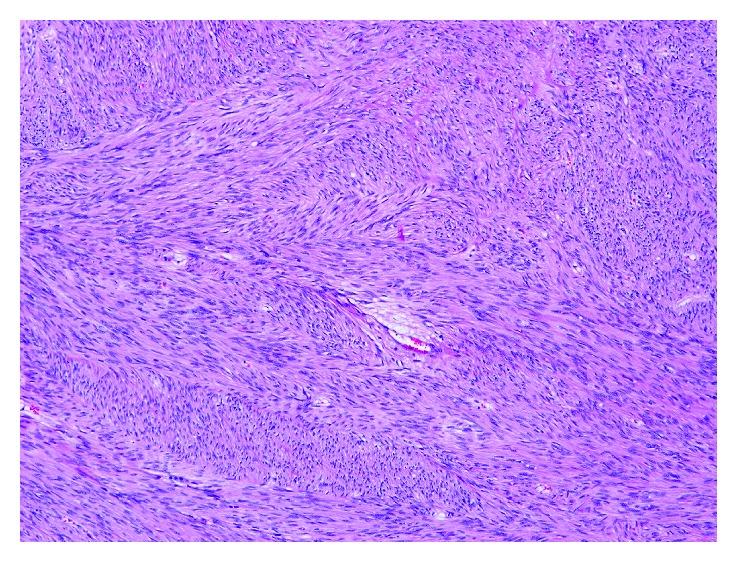

Pseudomyxoma peritonei (PMP) and extragastrointestinal stromal tumors (E-GISTs) are both rare entities. Most of the time, PMP is associated with an appendiceal tumor. An ovarian mucinous tumor can mimic appendiceal metastases. E-GIST is a mesenchymal tumor that can arise from the omentum, retroperitoneum, mesentery, or pleura. We present a case of an 87-year-old woman with mucinous carcinomatosis and acute intestinal occlusion submitted to an emergency laparotomy. She has found to have a borderline mucinous tumor of the ovary from the intestinal type with several lesions of pseudomyxoma peritonei and an E-GIST from the epiploons retrocavity (intermediated risk). In the literature, no relation was found between these two rare tumors. E-GIST was an incidental finding in the context of a mucinous carcinomatosis.

腹膜假黏液瘤(PMP)和胃肠道外间质瘤(E-GIST)均为罕见病症。大多数情况下,PMP与阑尾肿瘤相关。卵巢黏液性肿瘤可酷似阑尾转移瘤。E-GIST是一种间叶性肿瘤,可起源于大网膜、腹膜后、肠系膜或胸膜。我们报告一例87岁女性患者,因黏液性癌病和急性肠梗阻接受急诊剖腹手术。术中发现她患有肠型卵巢交界性黏液性肿瘤,伴有多处腹膜假黏液瘤病变,以及来自网膜后腔的E-GIST(中度风险)。在文献中,未发现这两种罕见肿瘤之间存在关联。E-GIST是在黏液性癌病背景下偶然发现的。